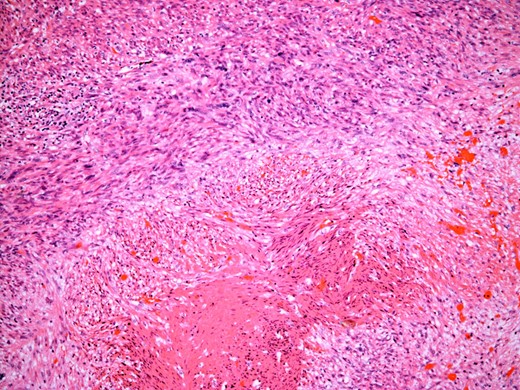

At the time of referral, the lesion had dramatically increased in size and become more symptomatic, therefore surgical excision was agreed. He underwent a trans-scrotal right epididymectomy where an irregular white mass measuring 15 × 46 × 35 mm3 was excised. Histological examination demonstrated a well delineated mass comprising fascicles of cytologically malignant spindle cells (Fig. 2). These showed moderate to nuclear pleomorphism, frequent mitotic figures, including atypical forms, and zones of coagulative necrosis (Fig. 3). Immunohistochemistry showed the tumour cells were strongly and diffusely positive for desmin, smooth muscle actin and h-caldesmon. FISH analysis for MDM2 amplification excluded a dedifferentiated liposarcoma, the main differential diagnosis at this site. Overall, the features were those of a paratesticular LMS, which was FNCLCC/Trojani grade 2.

On higher power, severe cytological atypia is evident, with frequent mitotic figures including atypical mitotic forms.